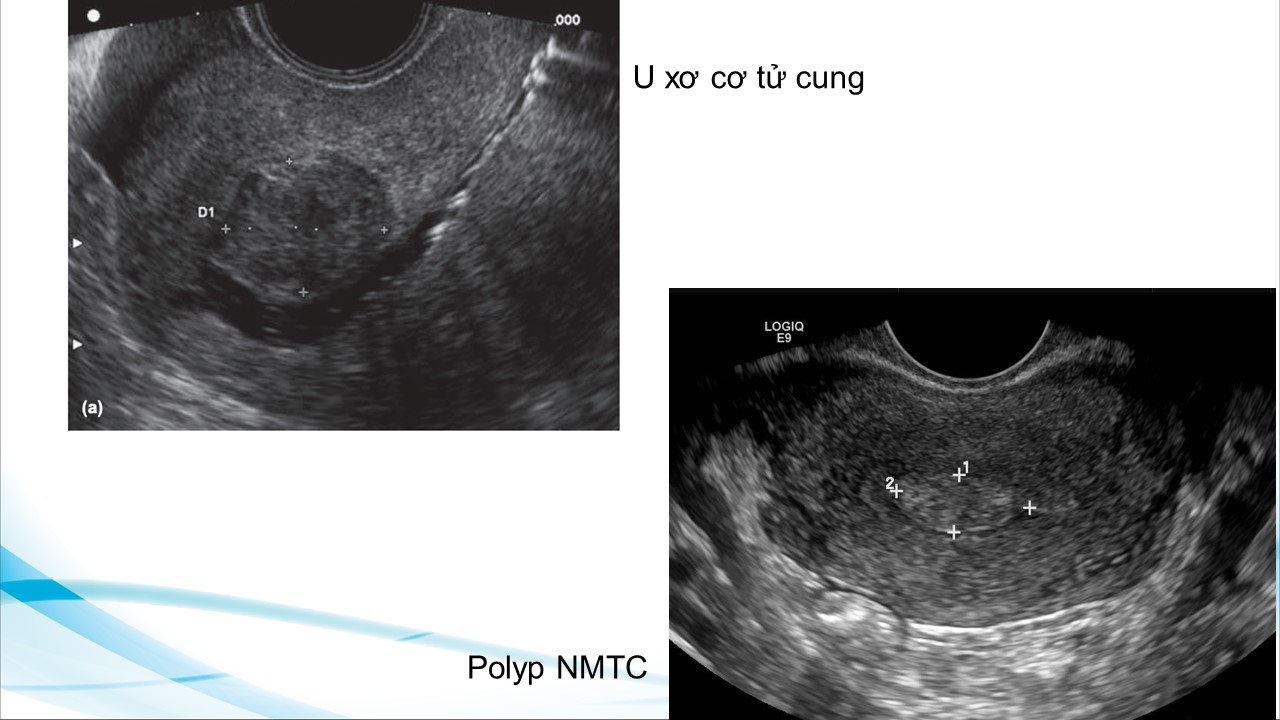

Siêu âm theo dõi trong bơm tinh trùng vào buồng tử cung và thụ tình trong ống nghiệm